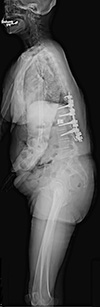

SONIALVISION G4

多目的性と検査効率,被ばく低減,省スペース化において実用性に優れ,様々な施設の要望に柔軟に対応するX線テレビシステム。スロットラジオグラフィ(オプション) により全脊椎や全下肢における高精度な計測が可能。また,泌尿器検査などで天板傾斜を行う際に観察部位の天板高さを変えずに天板傾斜が行えるUROモードを採用。